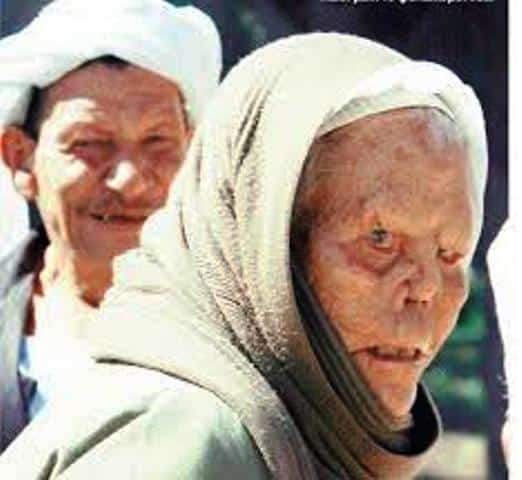

Η νόσος του Hansen ή αλλιώς λέπρα, είναι λοιμώδης νόσος που οφείλεται στο βακτηρίδιο Mycobacterium Leprae. Πρόκειται για μια βραδέως εξελισσόμενη νόσο η οποία μπορεί να προκαλέσει βλάβες στο δέρμα, στους οφθαλμούς και στο νευρικό ιστό.

Παρά την κακή της φήμη πρόκειται για μια ιάσιμη νόσο, η οποία αντιμετωπίζεται με αντιβιοτικά, ειδικά στην έναρξη εμφάνισης συμπτωμάτων. Για τον λόγο αυτό καθίσταται πολύ σημαντική η έγκαιρη ανίχνευση των συμπτωμάτων και η έναρξη αγωγής.Η νόσος δεν είναι πολύ μεταδοτική και ασθενείς οι οποίοι έχουν ξεκινήσει αγωγή είναι σε θέση να συνεχίσουν κανονικά τις δραστηριότητες τους.

Σύμφωνα με τον ΕΟΔΥ , ” Αυτή τη στιγμή στη χώρα νοσηλεύεται μια ασθενής 65 ετών με την νόσο αυτή, σε καλή κατάσταση και διεξάγεται ενεργητική επιτήρηση των επαφών της για εμφάνιση συμπτωμάτων.Στο παρελθόν έχουν εμφανιστεί παρόμοια περιστατικά στη χώρα, τα οποία αντιμετωπίστηκαν επιτυχώς.”